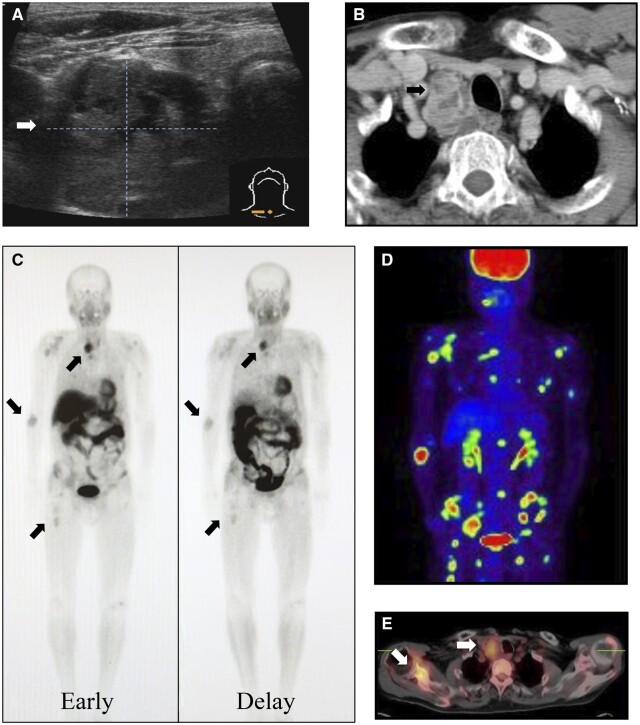

We present two rare cases of parathyroid carcinomas associated with multiple brown tumours. Plain radiographs, computed tomography, and neck ultrasonography revealed the presence of bone and parathyroid tumours. Despite the use of 99m Tc-methoxy isobutyl isonitrile (99mTc-MIBI) or 18F-fluorodeoxyglucose-positron emission tomography (18F-FDG PET)/CT, it was difficult to differentiate bone metastases from brown tumours. Parathyroid carcinoma was confirmed by histopathological examination following parathyroidectomy, resulting in spontaneous bone lesion improvement. In patients with parathyroid carcinoma presenting with bone lesions suggestive of metastasis, understanding the potential for brown tumour accumulation through 99mTc-MIBI or 18F-FDG PET/CT is pivotal. With this understanding, it is possible to diagnose brown tumours with parathyroidectomy and follow up for improvement of bone lesion and avoid invasive biopsy or surgery.